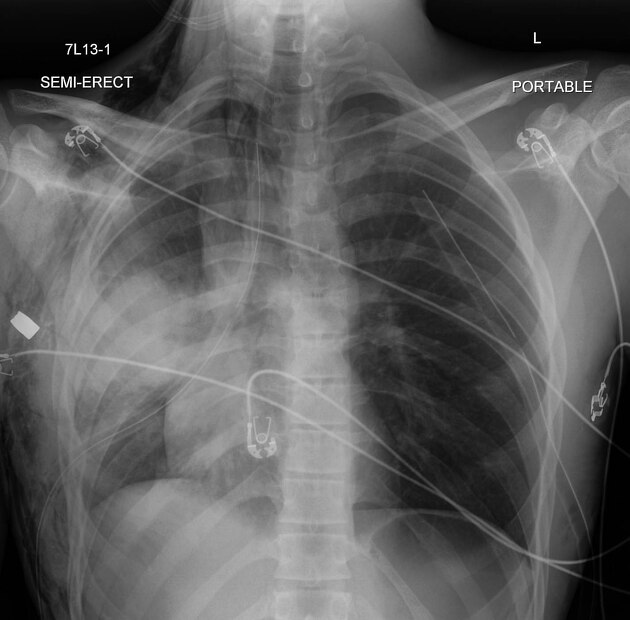

Describe the abnormality demonstrated (gunshot wound).

Subcutaneous emphysema over right axillary and right supraclavicular regions

Two ICCs (one per hemithorax) pointing superiorly, suggesting drainage of fluid from pleural space

Costochondral separation of bilateral eight, ninth, tenth and eleventh ribs

Mediastinal shift to the right

Small left-sided pneumothorax

Pulmonary consolidation in right mid-zone, likely to be a pulmonary contusion

Bullet remnant in right axillary region